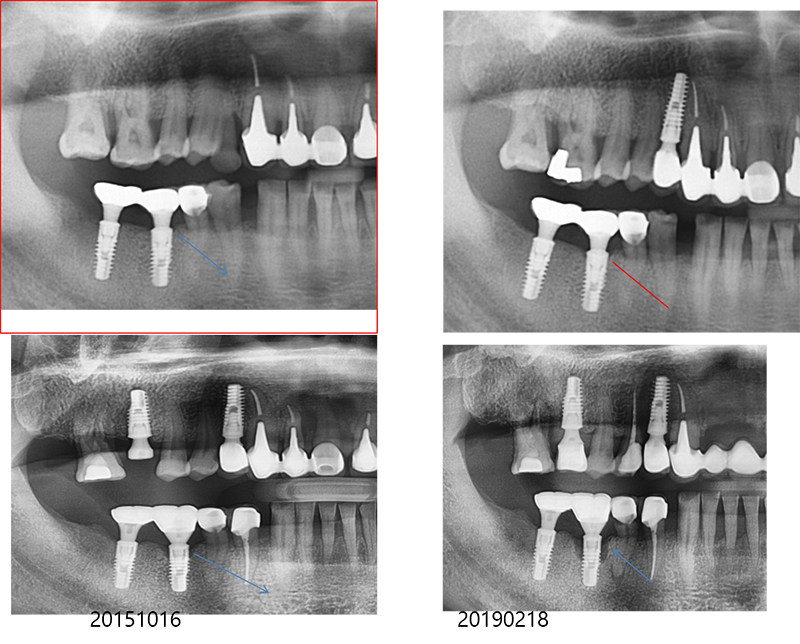

Bone loss

¿¡ µû¸¥ ÇȽºÃÄ ÆÄÀý

Ext. type 3.75mm Á÷°æÀÇ ÀÓÇöõÆ®.

Bruxism ÀÌ Àִ ȯÀÚ·Î½á ½É°í ±â´ÉÇÑ Áö 15³â ¸¸¿¡ ºÎ·¯Á®¼ ³»¿øÇß´Ù.

Á÷°æÀÌ 3.75mm·Î ¿¹Àü regular¿¡ ÇØ´çÇÏÁö¸¸ 4.0mmº¸´Ù ºÎ·¯Áö´Â °æ¿ì°¡ ¸¹´Ù.

¶ÇÇÑ ExtÀº º¸Ã¶ÀÌ ¿Ã¶ó°¡¸é Ç÷§Æû¿¡¼ 1.5mm °ñÈí¼ö°¡ °ÅÀÇ ÇÊ¿¬ÀûÀ¸·Î ÀϾÙ. À̹ø °æ¿ìµµ °ñÈí¼ö¿Í ±íÀº ¿¬°üÀÌ ÀÖ´Ù°í ¿©°ÜÁø´Ù.

37¹ø 4.3 Á÷°æÀÇ ¿øÇöõÆ®

Á¦°ÅÇÏ´Ù°¡ ÈìÁýÀÌ ³¯ °Í °°¾Æ¼ Æ÷±âÇϰí

´ÙÀ½¿¡ ¾à¼Ó Àâ¾Ò´Âµ¥ ȯÀÚµµ Àúµµ ¹Ì·ç´Ù°¡ ÀÌ Áö°æµÊ.

ÆÄ³ë¶ó¸¶ »ó

°á±¹ ÇȽºÃÄ Á¦°Å

¾Æ¸¶µµ ±³ÇÕ¿¡ ¹®Á¦°¡ ÀÖ¾ú´ø µí

37¹ø abutment ÆÄÀý, µÚÂÊ¿¡ 8¹øÀÌ º¸À̰í, fixture Á÷°æÀÌ 5.0, Á¶±Ý ÈìÁýÀÌ ³ªµµ µÈ´Ù´Â »ý°¢À¸·Î Á¦°Å¼ö¼úÀ»

Çß´Ù.

3¹ø¿¡

³ª´²¼ °Ü¿ì Á¦°ÅÇÑ °æ¿ì